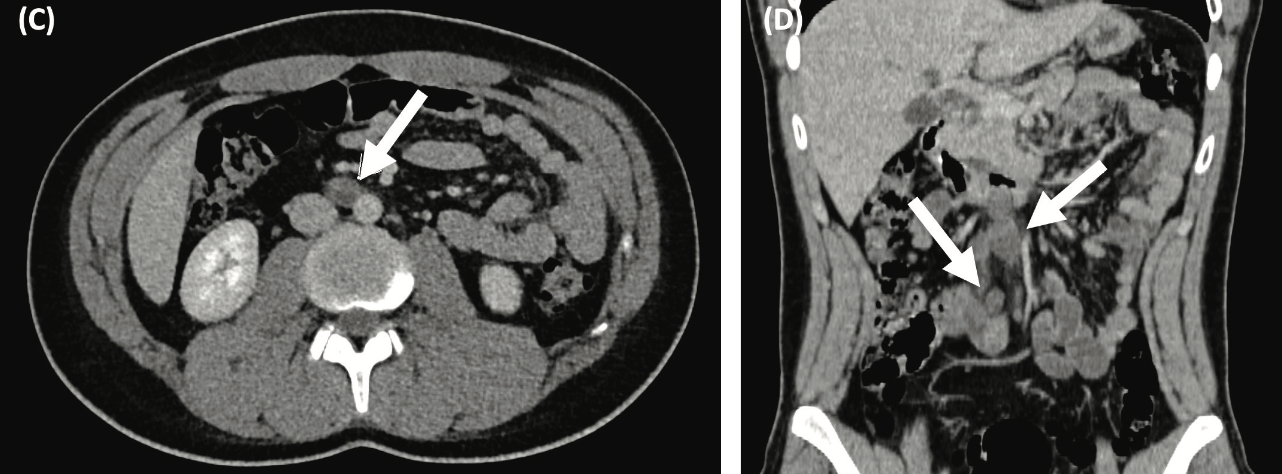

A right radical inguinal orchiectomy was performed. Pathological examination revealed a 2.4 cm by 2 cm embryonal carcinoma with tumor invasion into the tunica albuginea. Postsurgical tumor markers obtained 3 weeks after orchiectomy were β-hCG, 100.5 mUI/L (normal, <0.06 mUI/L); AFP, 1075 ng/mL (normal, 0-9 ng/mL); and LDH, 180 U/L (normal, 179 U/L). A chest, abdomen, and pelvis CT scan showed a 2.7-cm retroperitoneal lymph node enlargement, without visceral metastasis (Figure 1A and B).

Figure 1. Baseline and Follow-up Contrast Enhanced CT scans of a Nonseminomatous Germ Cell Tumor Before and After Systemic Treatment. Baseline axial (A) and coronal (B) CT scans show a 2.07-cm retroperitoneal lymph node enlargement.

Given the presence of node-positive disease with S2 serum markers, the diagnosis of a stage IIIB intermediate risk nonseminomatous germ cell tumor (NSGCT) was determined, and the patient underwent sperm banking. The patient was started on chemotherapy with 4 cycles of BEP (bleomycin, etoposide, and cisplatin), with a favorable tumor marker decline according to the Gustave-Roussy nomogram. After completion of the fourth chemotherapy cycle, serum tumor markers were negative, and 8 weeks after chemotherapy, the follow-up CT showed a 1.6-cm residual retroperitoneal lymph node conglomerate (Figure 1C and D).

(C, D) Follow-up axial and coronal CT scans after 4 cycles of bleomycin, etoposide, and cisplatin (BEP) show a partial response to systemic therapy with a residual retroperitoneal disease of 1.64 cm (arrow).